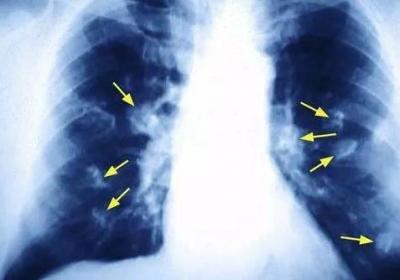

发布时间: 4月前肺癌大户被揪出!世卫组织:致肺癌能力仅次于吸烟,你家可能就有,肺癌大户被揪出!世卫,组织:致肺癌能力仅次,于吸烟,你家可能就有...

发布时间: 4月前揪出引发女性肺癌的罪魁祸首 厨房油烟的危害远超乎想象,揪出引发女性肺癌的罪,魁祸首 厨房油烟的危,害远超乎想象...